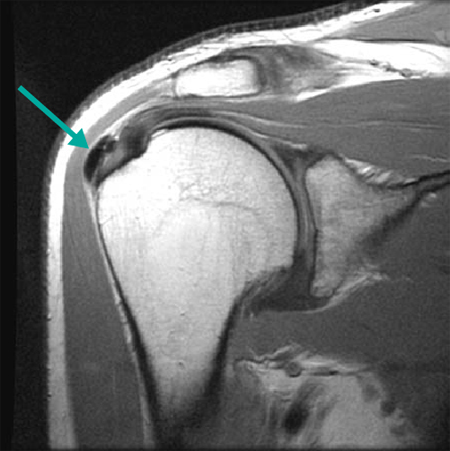

Ressonância nuclear magnética (RNM) demonstrando tendinopatia por calcificação envolvendo o supraespinhal central distal

Do acervo pessoal de James Wang, PhD